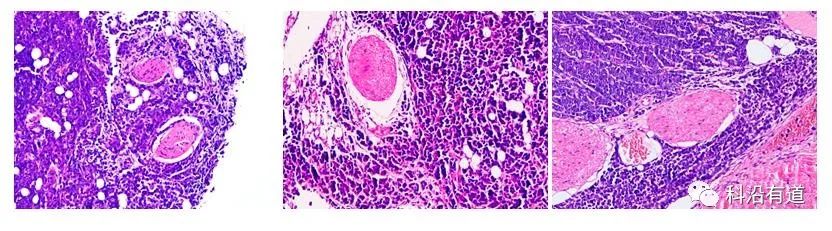

(三)主体内容:外周神经浸润(PNI)是复杂的病理过程,涉及肿瘤细胞、神经纤维及肿瘤基质,缺乏理想疾病模型限制了PNI的研究。较早期体外研究利用Boyden小室铺Matrigel胶模拟基底膜,寻找和验证与肿瘤侵袭或转移相关神经营养因子,但这种方法未能直接说明肿瘤细胞浸润神经。坐骨神经浸润模型即将肿瘤细胞接种于坐骨神经鞘内,模拟神经微环境,观察肿瘤细胞在神经内的生长特性及其对坐骨神经的浸润情况。Mashour等首次建立坐骨神经浸润模型,用于评估溶瘤病毒对神经转移瘤的治疗效果。此模型通过评估动物坐骨神经的功能间接评估肿瘤PNI情况,为实验过程中PNI程度提供了一个可观察指标。

坐骨神经浸润模型可通过观察坐骨神经功能间接评估PNI,但此时肿瘤已经显著长大、浸润坐骨神经,而PNI的发生早期可能只涉及少量肿瘤细胞,在明显成瘤前已经开始。由于坐骨神经较为表浅,走形固定,较多研究者通过B超、MRI等影像检查手段评估肿瘤与神经的关系,即神经变粗、周围有组织增生等。但影像学改变是肿瘤沿神经转移间接证据,并不能直接说明是肿瘤细胞侵犯神经,最终仍需将动物处死后进行病理学检验证实。

2)麻醉机麻醉裸鼠,75%酒精消毒皮肤,暴露左侧坐骨神经深达股二头肌。应用显微注射法将MiaPaCa2细胞注入坐骨神经的神经束膜,远端直达胫神经和腓总神经分叉处。细胞浓度为1×10^5/μL,应用注射器2min内缓慢注入10μL癌细胞悬液,建立坐骨神经浸润模型。

1)6周后,摘取移植瘤,拍摄大体照片;

2)福尔马林固定,石蜡包埋,进行HE染色。